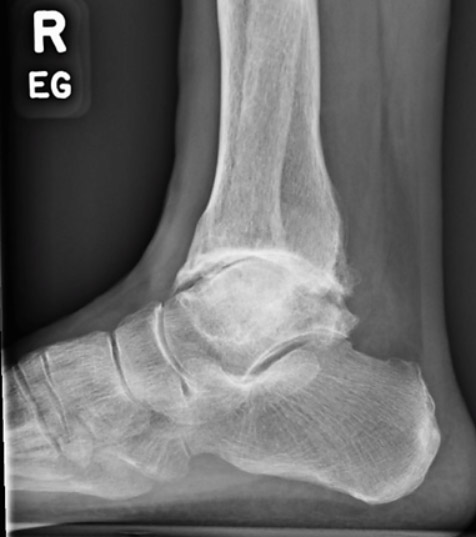

Example of x-rays showing advanced (end-stage) arthritis. Compared to the photo below (of a healthy ankle), the joint space is significantly narrowed or absent and there are many bone spurs throughout.

X-ray's of the same ankle before undergoing ankle replacement.

X-ray's of the same ankle before undergoing ankle fusion.